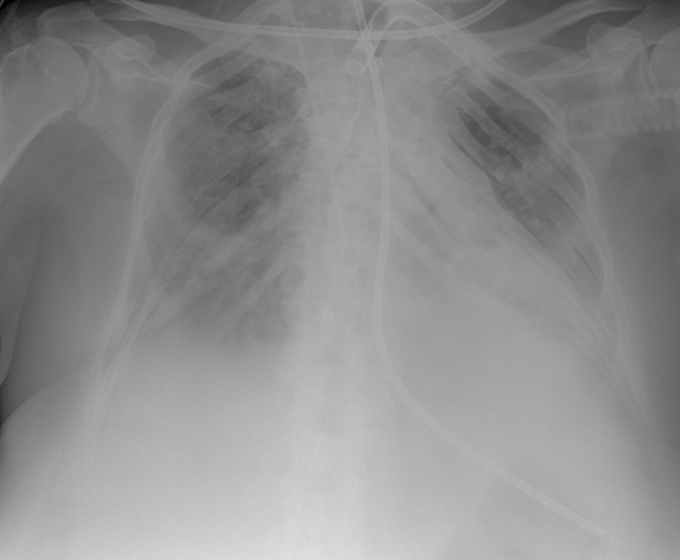

56 year old patient with dyspagia. A tumor of soft tissue was described in upper mediastinum on plain X-ray of the thorax. What is this mass in the upper mediastinum?